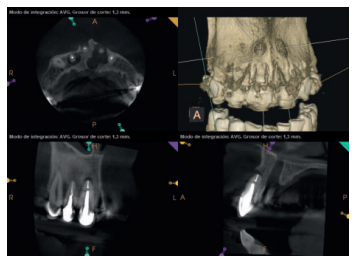

Para confirmar el origen endodóntico y el tamaño de las lesiones se realizaron exploraciones tomográficas con espesor de corte de 75 micras mediante CBCT CS8100 (Carestream Dental® ) en las que se evidenciaron lesiones periapicales radiolúcidas a nivel de 12, 11, 21 (con afectación bicortical), 25 y raíces vestibulares de 26 (Figuras 4 a 8).

En los dientes 12, 11 y 25 el defecto óseo presente es de pequeño tamaño (estimado en 0,2, 0,03 y 0,05 cm3 , respectivamente) con ausencia de una pared y que, tras el abordaje quirúrgico, ostectomía con fresado óseo del área apical y legrado, presentan una arquitectura favorable para la regeneración espontánea, por lo que la actitud más razonable fue no aportar biomateriales para intentar mejorar la regeneración ósea.

Por otro lado, la situación inicial de la pieza 21, con un defecto de 0,35 cm3 de dos paredes opuestas de espesor total vestíbulo-palatal, que llega al alcanzar el pedículo vásculo-nervioso nasopalatino sin solución de continuidad, nos hace plantear una estrategia distinta a la anterior.